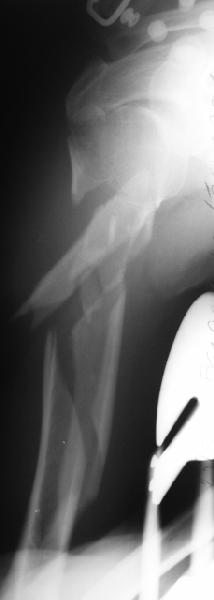

Although we can not see exactly the head piece, and assuming that there are not signs of infection, my suggestion would be to do some type of "bridging" procedure : implant fixation in head piece and distal main fragment, and the rest to be left on its soft tissue attachments (living bone graft).

I just did this attached case, using 90 degrees angled blade plate, and this would be my preference in all similar cases.

Well, to date he is still on abduction splint with traction applied to a wire placed through the olecranon. Images attached. The acetabulum

was ORIFed. The humerus is still discussing...

The views you now show demonstrate an extra articular fracture with good alignment on the AP, and some displacement on the lateral.

This should be able to be managed with adjustment of the traction.

Ilizarov is probably the best fixation if you decide to do so. However, it will heal with nonoperative treatment, with painless, reasonable

function. Even if it does not heal primarily, the pieces will heal enough to become a single level problem, readily solved with compression

plating. Jim Carr